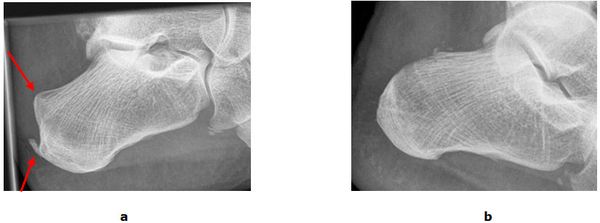

Abb.3: a Sehnensporn und Haglund Exostose im präoperativen Röntgenbild. b Das Fersenbein ist modelliert und die störenden Knochenüberstände wurden entfernt. Der Patient kann wieder schmerzfrei laufen.